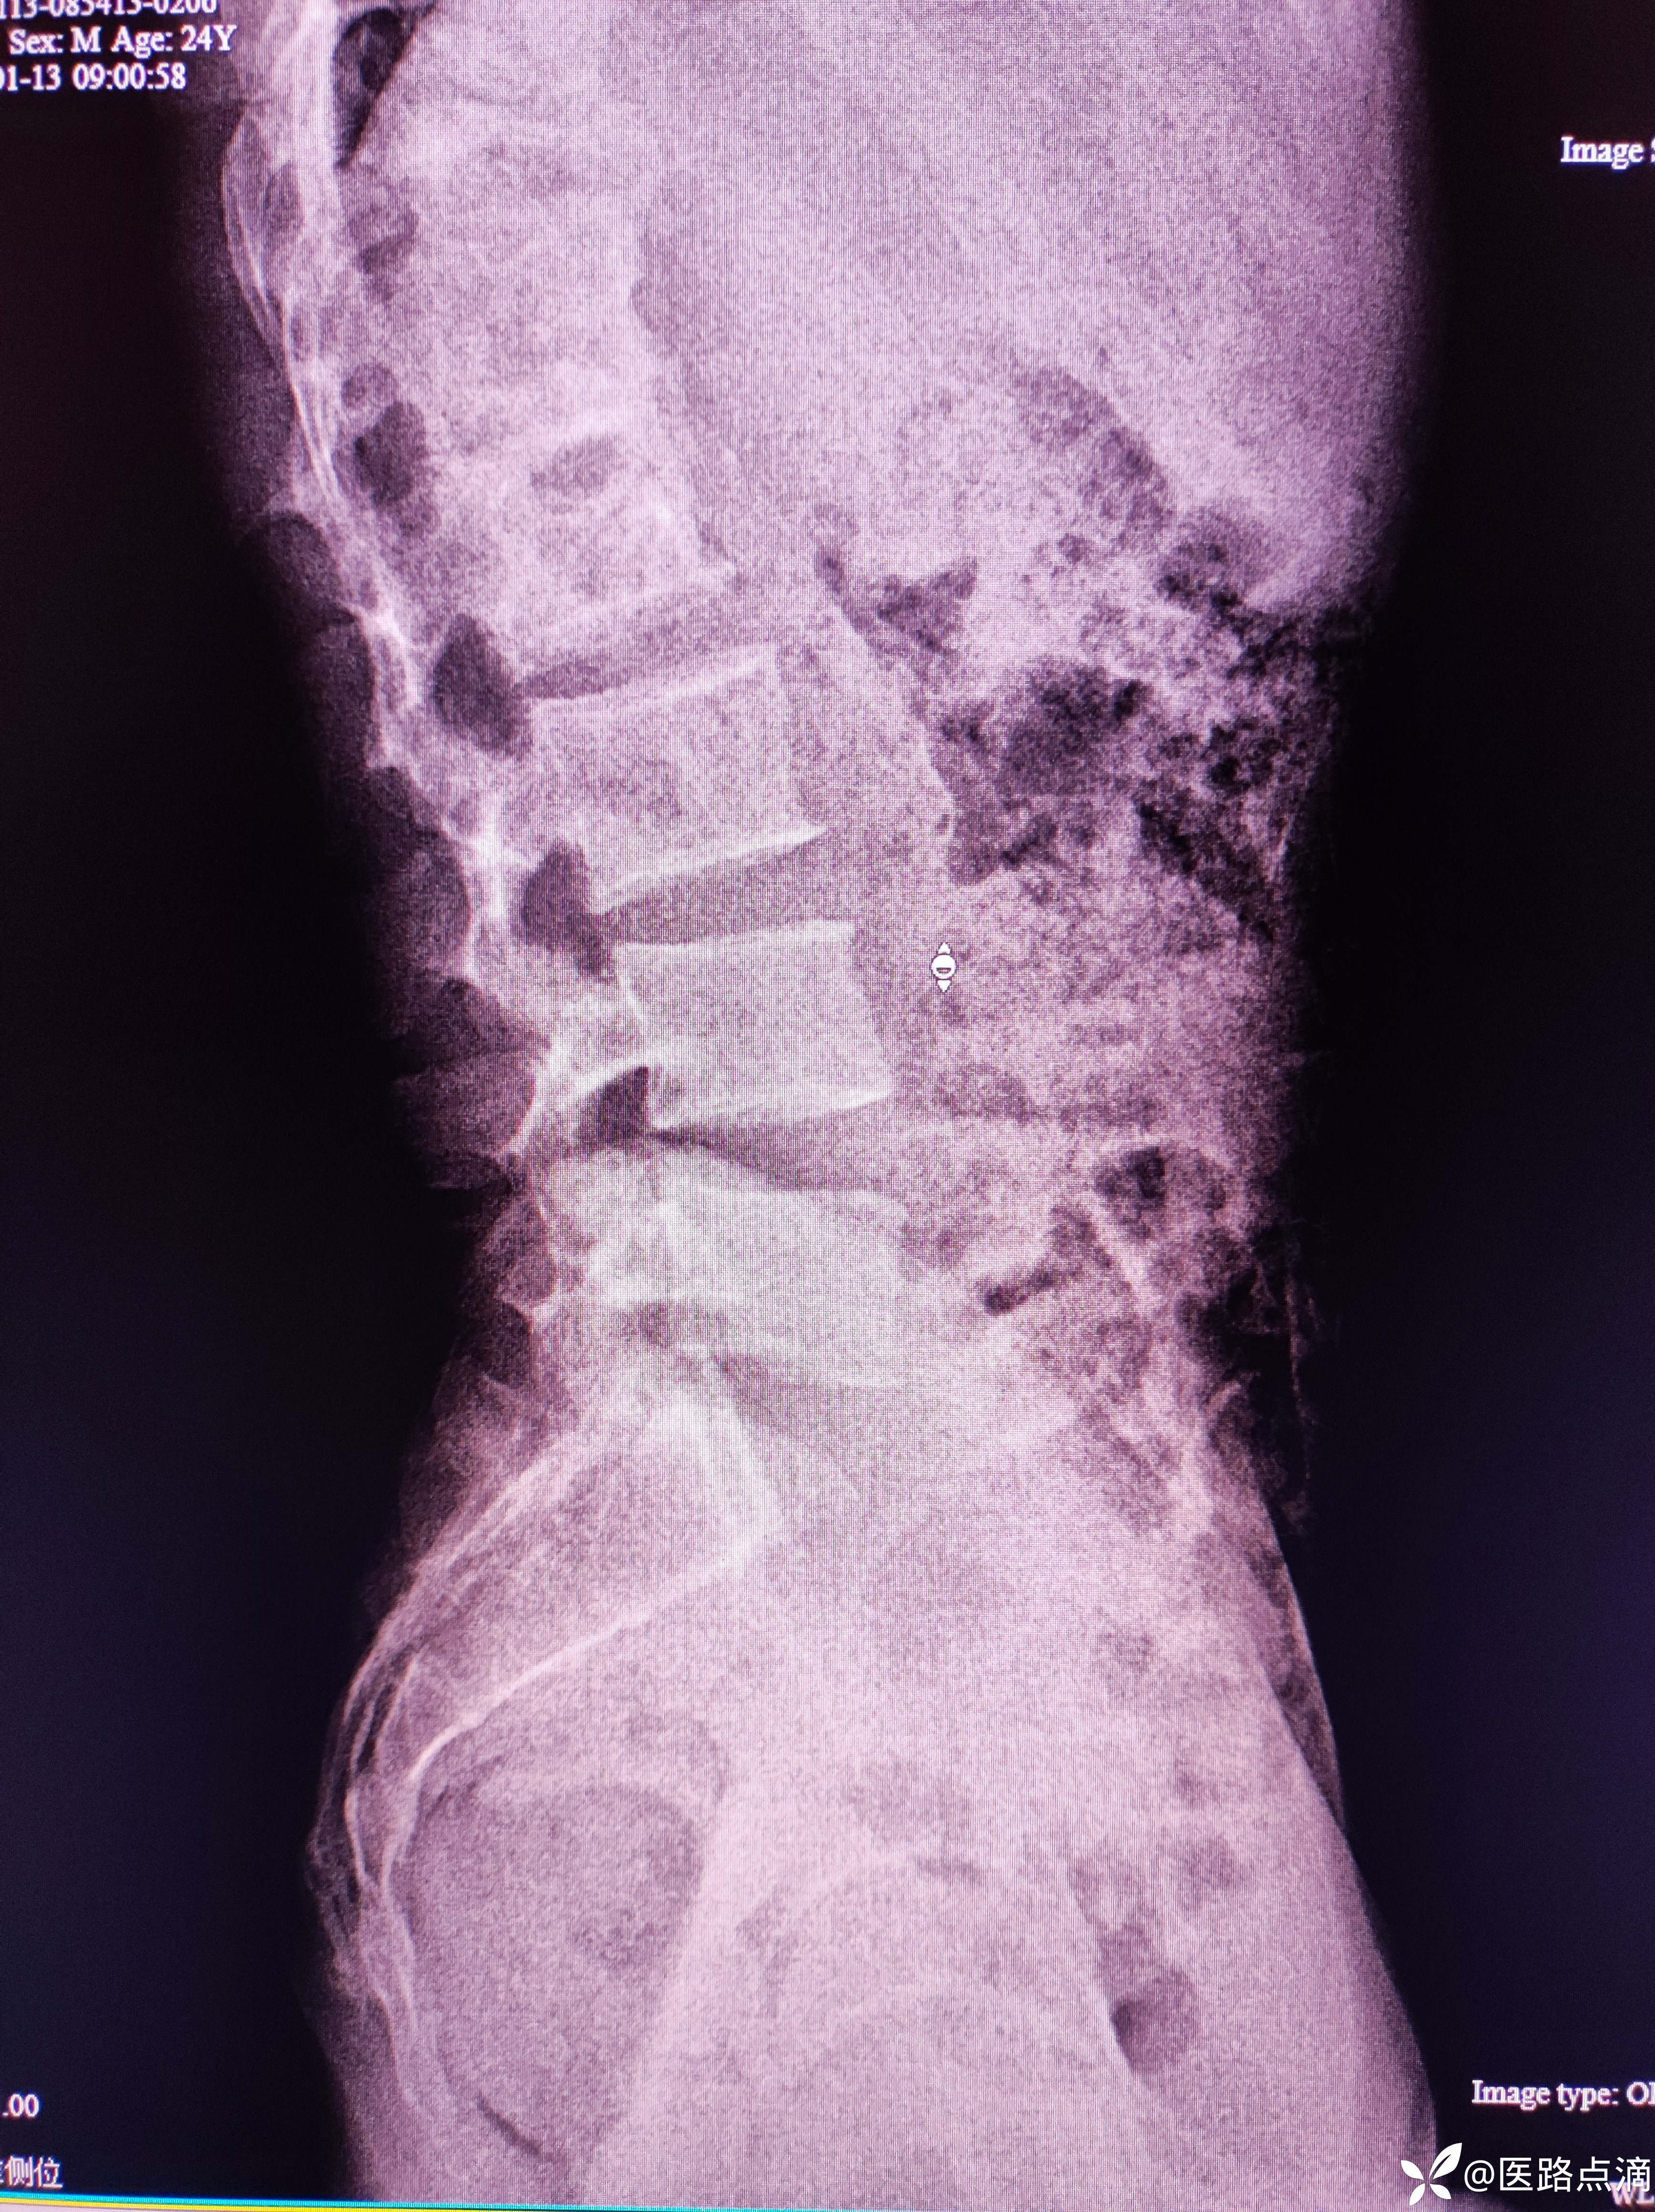

病史:患者青年男性反复腰痛七个月。三个月前来门诊就诊,当时诊断腰肌劳损,应用外用药物活血化瘀的膏药,治疗效果不佳。两个月前,患者再次来诊。脊柱X线显示患者患者存在脊柱轻度侧弯,让患者做腰背肌功能锻炼,注意平时脊柱姿势。

患者在上级医院就诊诊断胸腰椎结核。

随访后续治疗该患者转诊至北京进行手术治疗术后患者,疼痛明显缓解。回过头来再看当时的片子,发现胸腰椎结合处椎体显示不清,有模糊影,当时未引起足够重视。